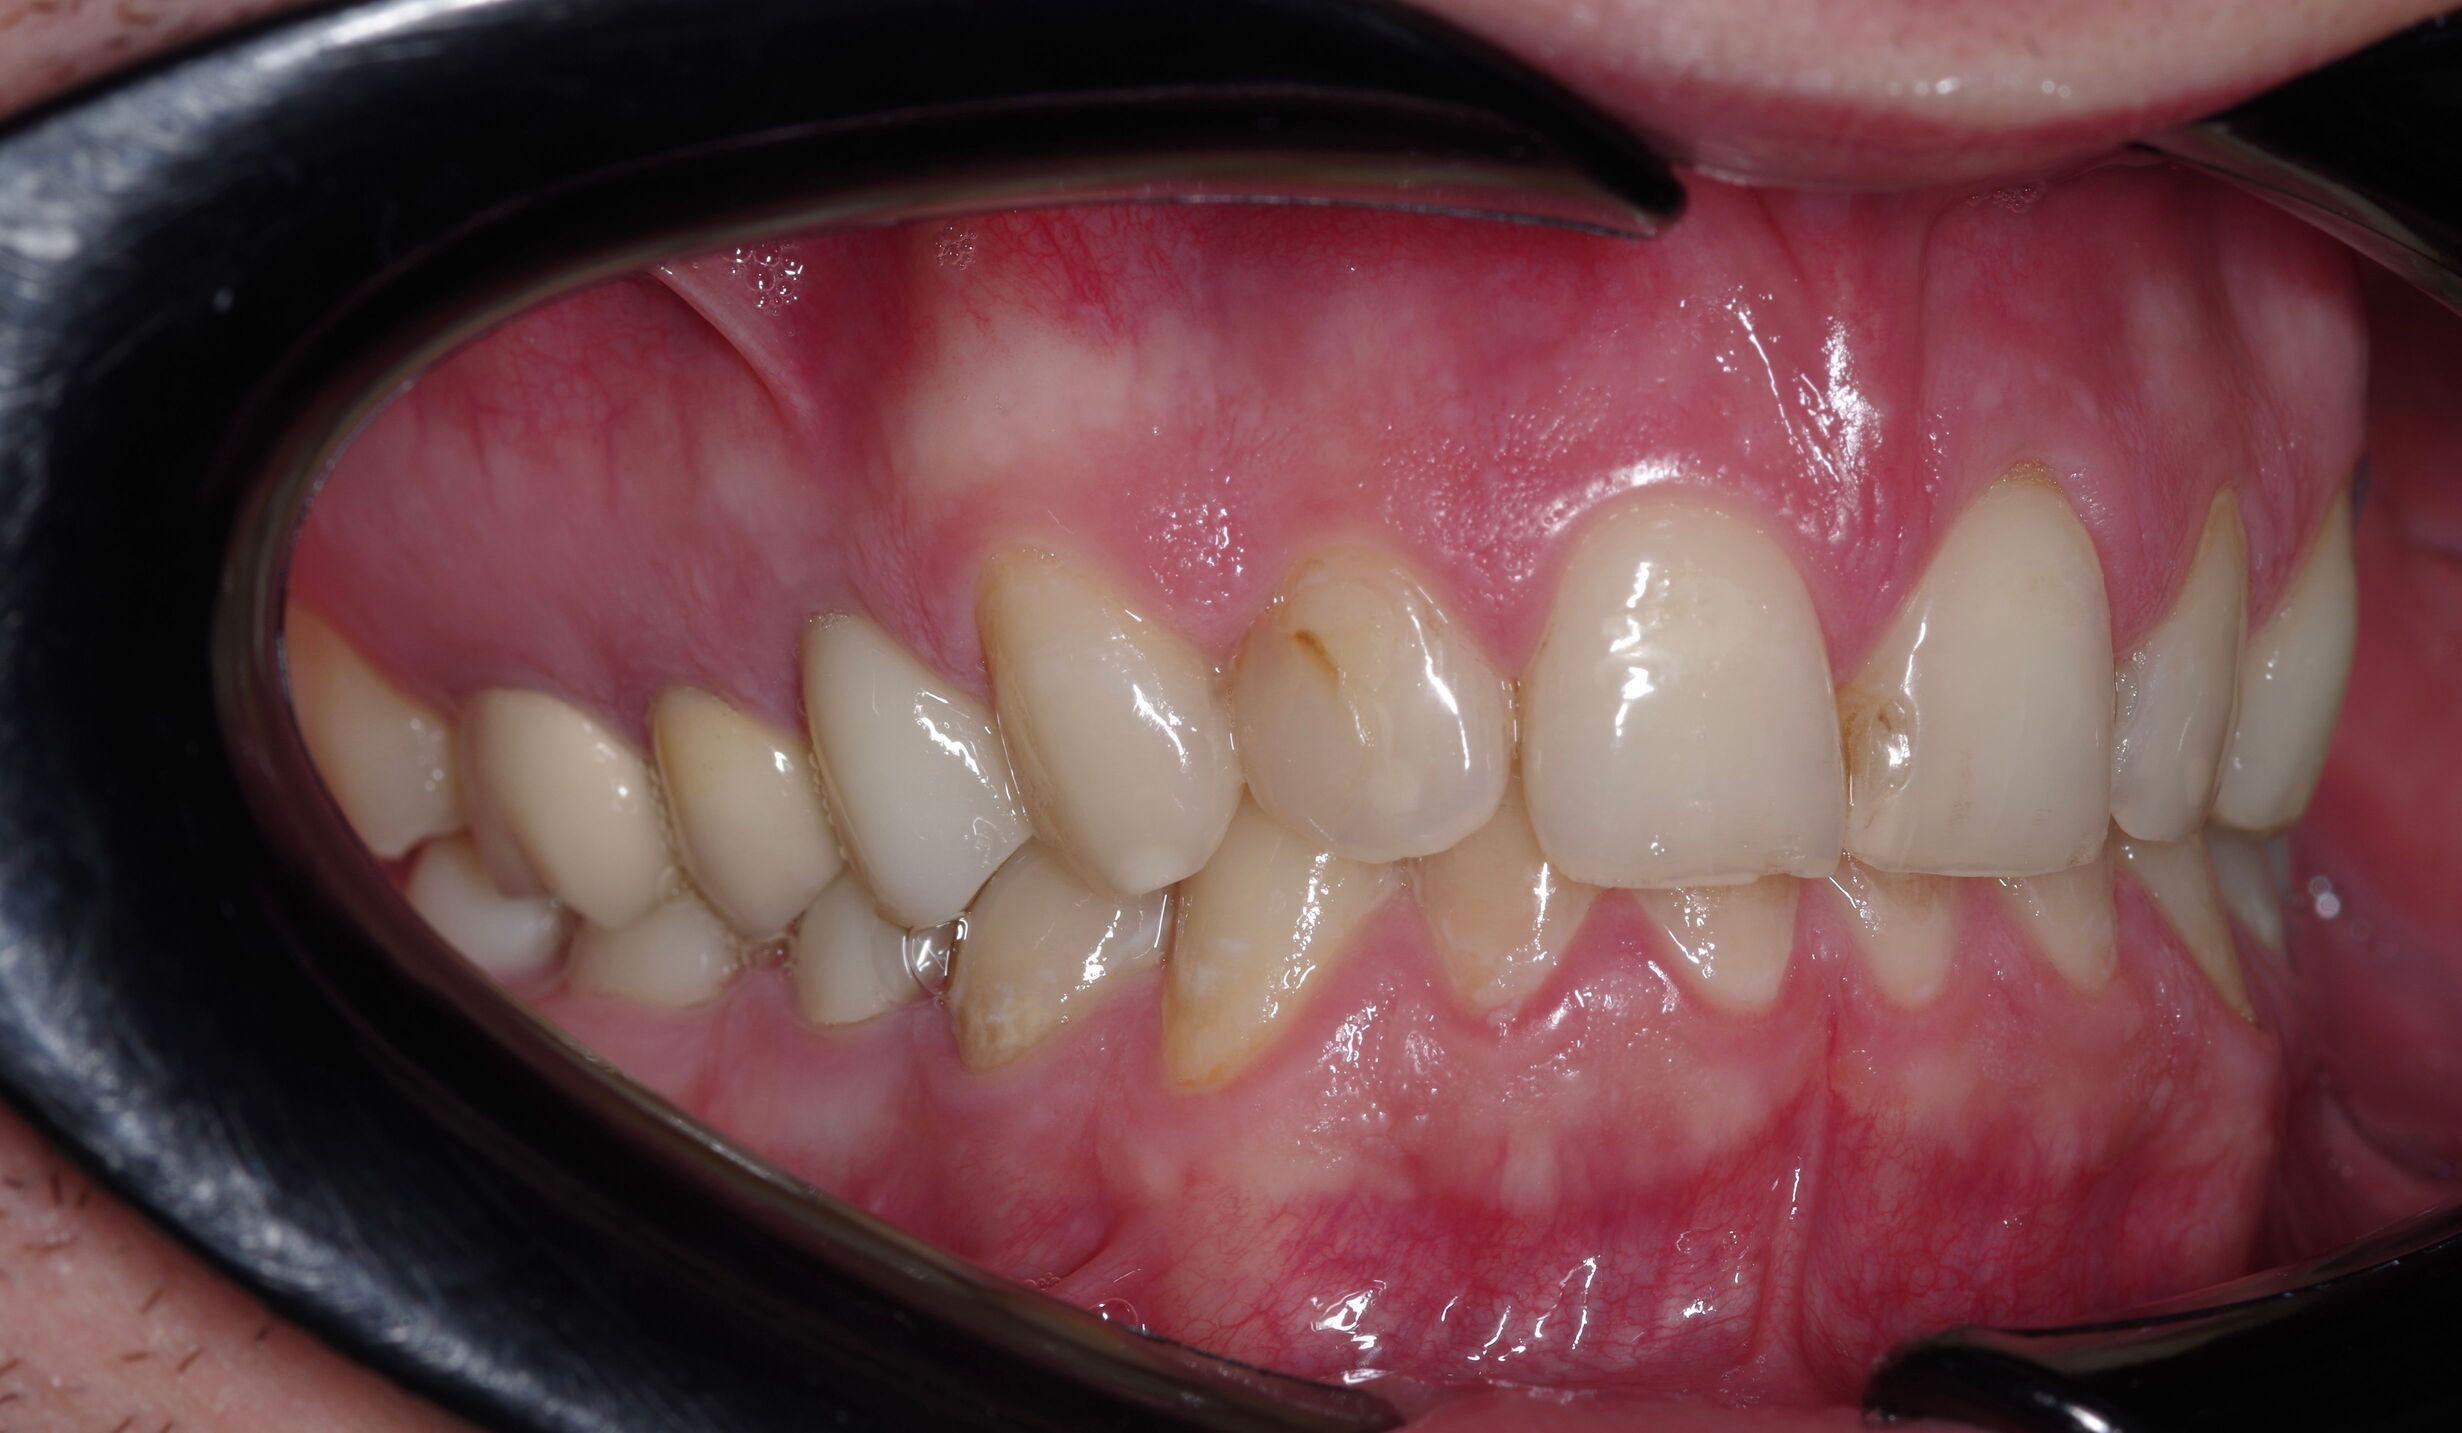

Виниры E.max — это современное решение в эстетической стоматологии, позволяющее вернуть зубам идеальную форму, цвет и прочность. Они изготавливаются из стеклокерамики (дисиликата лития) и относятся к категории премиальных керамических виниров, известных под брендом E.max. Они изготавливаются из литий-дисиликатной керамики, которая обладает уникальными эстетическими свойствами и высокой биосовместимостью. В данной статье мы подробно рассмотрим, что такое виниры E-max, их преимущества и недостатки, показания и противопоказания к установке, этапы установки, срок службы и рекомендации по уходу за ними.

Литий-дисиликатная керамика, используемая для изготовления

виниров E-max, отличается высокой прочностью и устойчивостью к сколам и трещинам. Благодаря этому, виниры E-max можно устанавливать на передние зубы, обеспечивая им долгий срок службы и максимальную эстетику. Виниры E-max имеют естественный оттенок и прозрачность, что делает их незаметными на зубах и позволяет создать красивую улыбку.

- Эстетические дефекты. Виниры E.max с работой под ключ особенно эффективны при эстетических дефектах передних зубов: диастемах, сколах, трещинах, неравномерной форме.

- Неправильная форма зубов. Коррекция формы зубов для улучшения их внешнего вида.

- Изменение цвета зубов. Виниры E-max могут использоваться для маскировки стойких пятен и изменения цвета зубов, которые не поддаются отбеливанию.